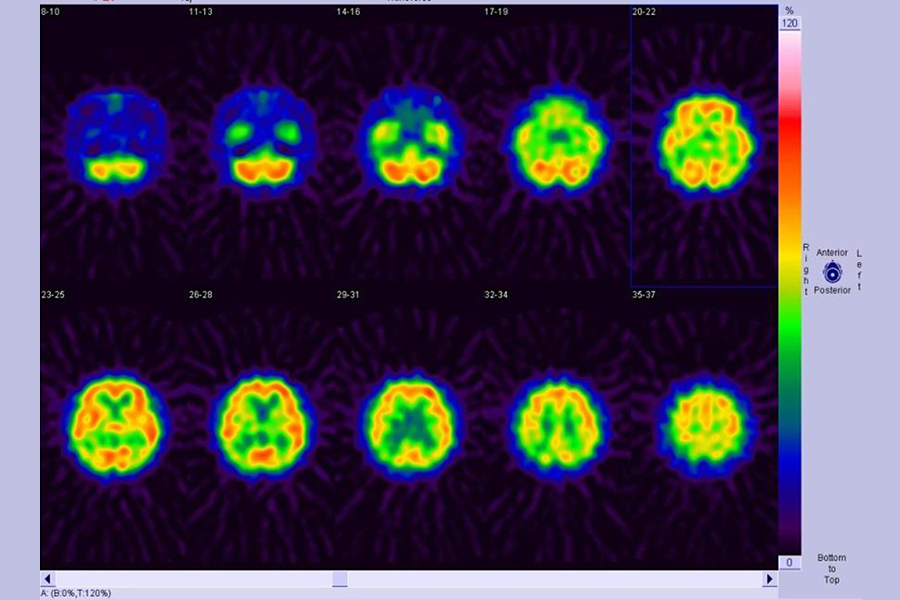

脳血流シンチグラフィー

脳の血流状態を画像化して、脳の機能異常を診るために行われます。脳梗塞や認知症の早期発見や脳梗塞における治療の適応、治療効果の判定などに有用です。検査時間は1時間程度で、特に検査前の処置は必要ありません。(図1脳血流シンチ画像)